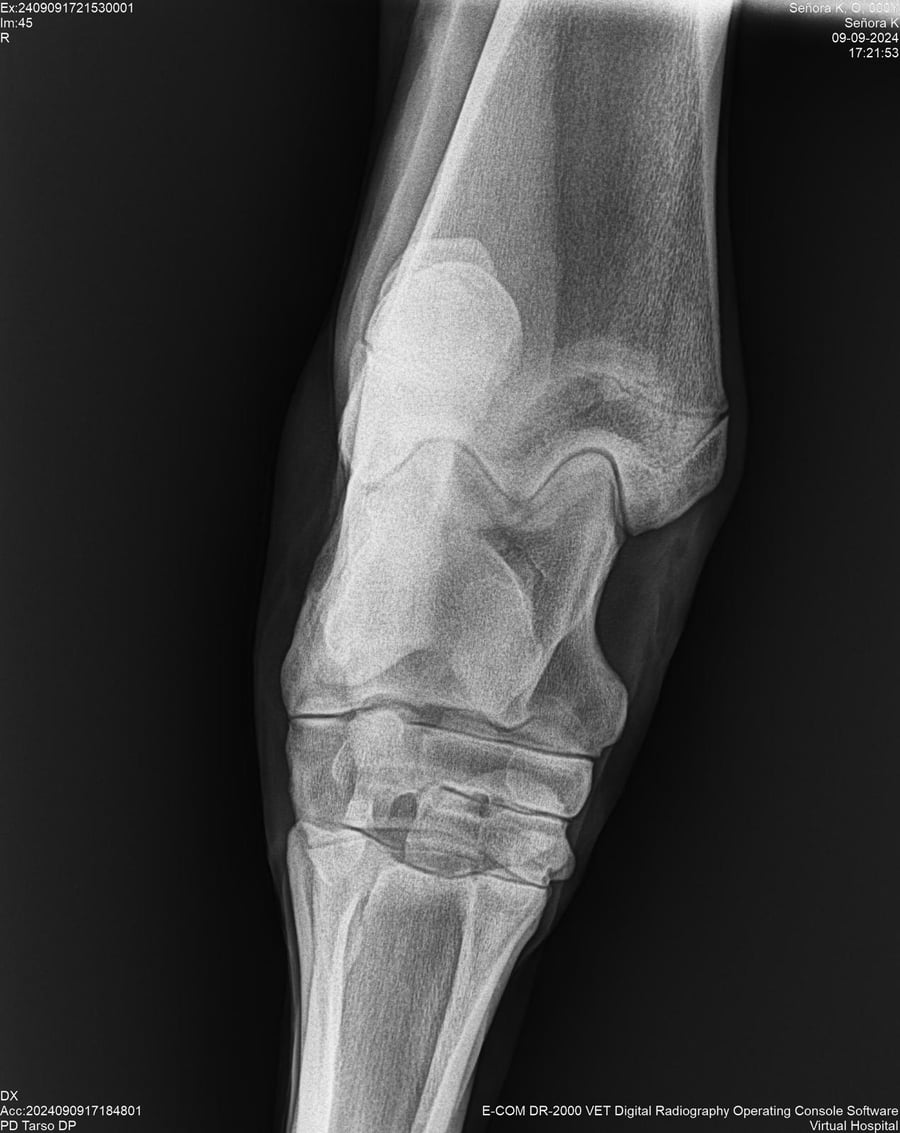

LOTE 44, SEÑORA K

Identificador: #291147-

Generacion 2022